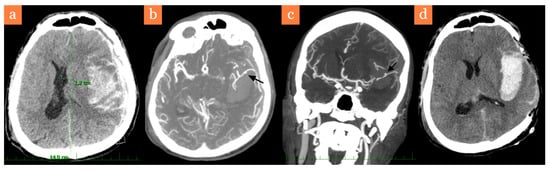

2. Case Report